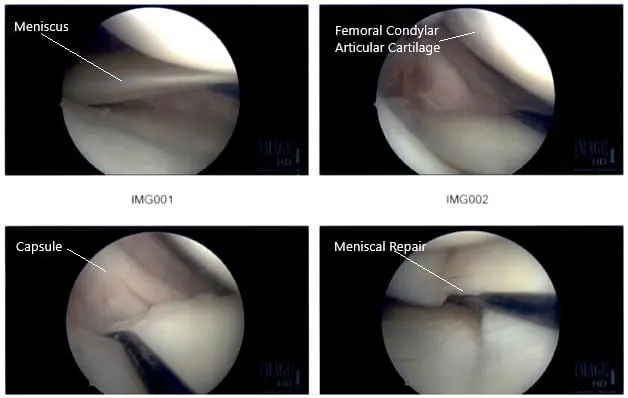

Intraoperative Arthroscopic Images of the right knee.

There was no ligament laxity. Preoperative antibiotics were given. The right lower extremity was prepped and draped in an aseptic condition. The tourniquet was inflated. A lateral entry portal was made and the arthroscope was introduced. The patellofemoral joint was examined and the medial compartment was examined and there was a near-complete tear of the posterior horn of the medial meniscus from the capsule.

Intraoperative Arthroscopic Images of the right knee.

The decision to repair it was taken. The margins were probed using rasp and shaver. The meniscus was approximated onto the capsule and fixed using FasT-Fix Nephew curved x2. Good opposition was achieved. The sutures were cut after the notch. The all-inside technique was used. Final pictures were taken.